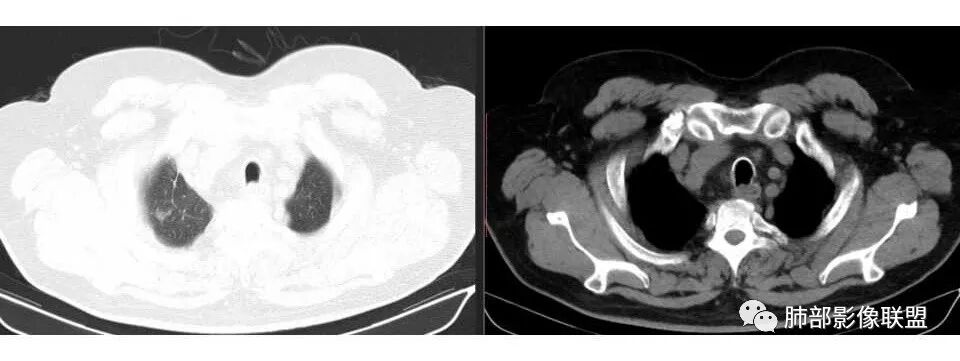

市医院--时建文: 右肺门占位性病变伴纵隔淋巴结肿大,鳞癌?小细胞癌?淋巴瘤待除外,右肺上叶结核。

甄德强:小病灶大转移,小细胞肺癌。

wkj: 40岁以上吸烟男,右肺上叶新生物,纵隔新生物大于肺新生物,纵隔呈融合,冰冻,气管外压,血管疑似未受累,仅包绕,考虑小细胞。

张帅: 患者以肢体无力就诊,既往有吸烟史,胸CT:右肺门占位性病变,密度不均,病灶内病灶内支气管明显狭窄,走行僵硬,病灶边缘光滑,呈浅分叶,未见明显毛刺,对中叶支气管明显挤压。右肺内可见散在片状实变影,前纵隔淋巴结明显肿大,内可见低密度区,2r 4r 7 10r淋巴结明显肿大。诊断考虑恶性方向,肺癌(小细胞)并纵隔肺门淋巴结转移?淋巴瘤?

1.右肺上叶不规则结节影,右肺门及纵隔多结节并形成巨大块影,密度均匀,沿途支气管明显狭窄。

原发灶小或隐匿,肺门纵隔淋巴结异常增大,所谓“娘小崽大”常见于肺小细胞癌!